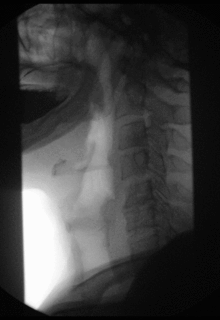

الكشْف الفَلْوَريّ أو التَنْظيرٌ التَأَلُّقِيّ[1] (بالإنجليزية: Fluoroscopy)، طريقة تشخيص طبية تستخدم الأشعة السينية. تمكن الطبيب من رؤية التركيب الداخلي والعمليات في الجسم، وتعطي صورة بالأشعة السينية لأعضاء الجسم، تعمل بالفعل. يختلف الكشف الفلوري عن التصوير بالأشعة، وهو عملية الأشعة السينية الشائعة التي تعطي صورة ثابتة على فيلم. ويستخدم الجراحون الكشف الفلوري لرؤية الأعضاء القاصرة عن الأداء، ولمراقبة الإجراءات الطبية، مثل إدخال قثطار، (أنبوب) في شريان وإزالة الأجسام الغريبة من الرئتين، أو المعدة.

وقبل إجراء الكشف الفَلْوَريّ على القناة الهضمية، يشرب المريض سائلا يحتوي على إحدى مركبات الباريوم. فالباريوم يمتص الأشعة السينية بقوة، ولذلك تظهر الأعضاء الهضمية بوضوح أكثر في الصورة. يرقد المريض علي طاولة، وتُركَّب أنبوبة الأشعة السينية تحت الطاولة. ويعلَّق جهاز يسمى مكثف الصورة فوق المريض. فتشكل الأشعة السينية المارة عبر جسد المريض صورة غير مرئية على مكثف الصورة. ويحول مكثِّف الصورة الأشعة السينية إلى صورة مرئية تسجلها آلة تصوير تلفازية، فيري الطبيب هذه الصورة على شاشة التلفاز.